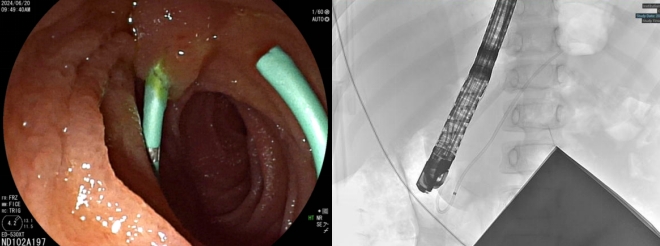

鉴于患者年龄小,对放射性敏感性高,术前医疗团队对患儿实施了严密的防护措施,并尽量缩短手术时间以减少射线对患儿的伤害。术中黄永辉使用十二指肠镜,顺利进入十二指肠降部并定位胰管开口。胰管插管比胆管插管技术要求更高,内镜下可见患儿肠腔较成人明显狭窄,操作空间十分有限,插管面临着极大的挑战。黄永辉凭借丰富经验,使用切开刀带导丝顺利插入胰管并完成胰管插管,然后沿导丝精准置入5Fr*9cm胰管支架。造影显示支架位置良好、引流通畅,手术顺利结束。

图为胰管支架置入